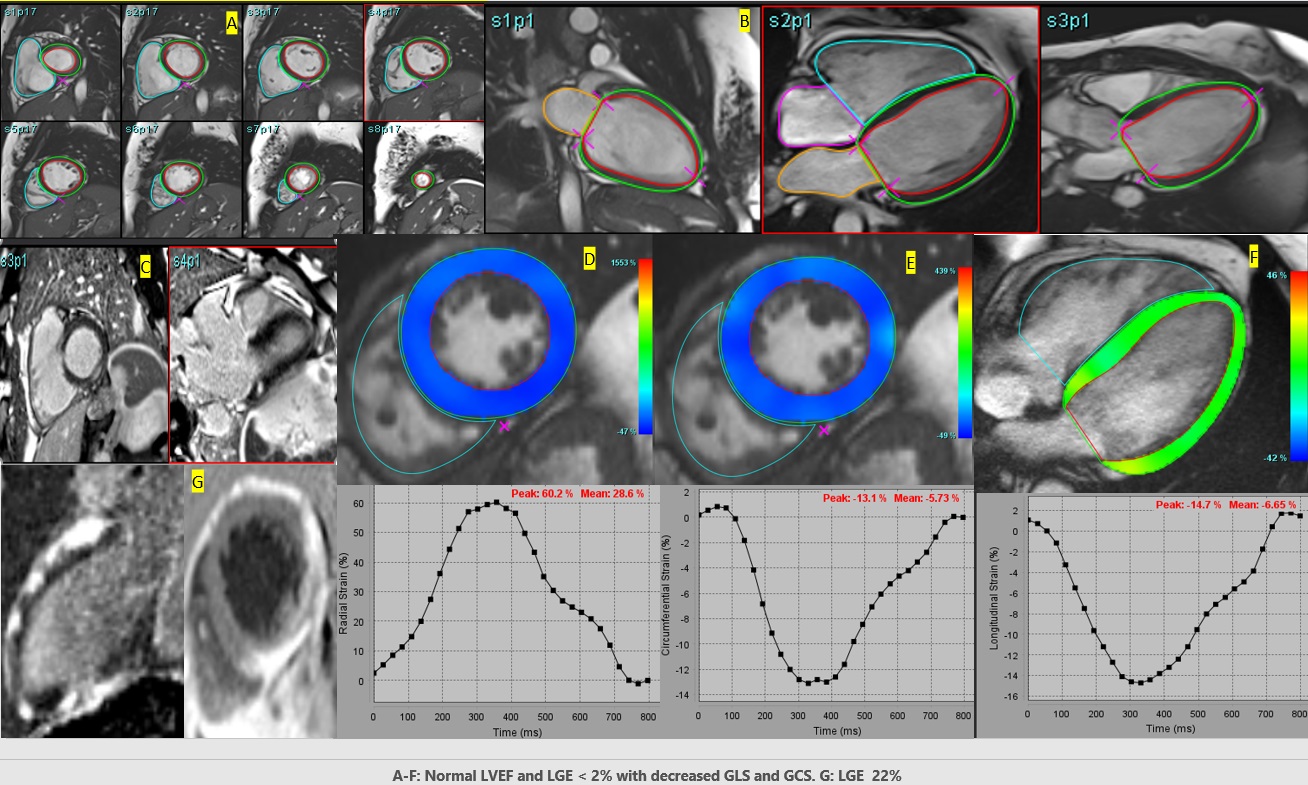

LVAD= left ventricular assist device, HFH= heart failure hospitalization, VT= ventricular tachycardia, VF= ventricular fibrillation, LVEF= left ventricular ejection fraction, LGE= late gadolinium enhancement, LV= left ventricle, LAX= long axis, SAX= short axis, ref= reference level. Figure 1: A-F: Decreased global longitudinal (GLS) and circumferential strain (GCS) with normal LV ejection fraction and LGE < 2% of LV mass. G: Marked LGE of 22% of the LV mass. *A: Short axis segmentations for left ventricle (LV) endocardial and epicardial borders from base, mid to apical segments. B: Long axis segmentation for LV showing mitral valve annular plane (X) and the apex (X) with endocardial and epicardial borders. C: Phase-Sensitive Inversion Recovery showing late gadolinium enhancement (LGE) involving basal inferior and inferior-lateral wall in different planes. D: LV short axis normal radial strain E: LV short axis decreased circumferential strain (Peak strain -13.1%) F: LV long axis decreased peak strain -14.7%. .jpg)